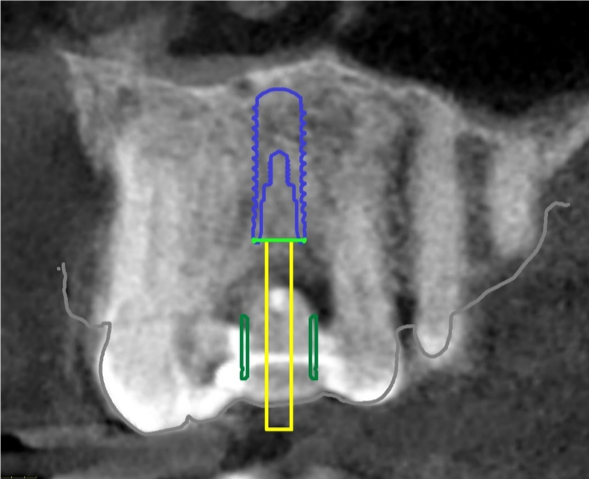

The CBCT and digital scan were placed in software to merge the two. Figure 8 shows the superimposition of the scan over the CBCT. The clinician used the volumetric data to determine implant size, depth, and position. The surgeon, dentist, and laboratory were all involved in a conference call to go through several different implants. They chose the implant size and length based on the position of the sinus, the width of the alveolus, and the appropriate position for an ideal surgical result.

Fig 8. Superimposition of digital scan over the CBCT.

Figure 8

Fig 9. Implant in place digitally.

Figure 9